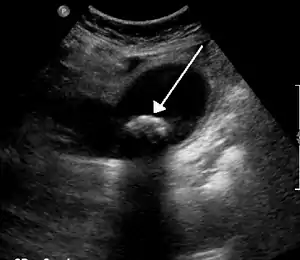

Diagnosis is typically confirmed by abdominal ultrasound. Other imaging techniques used are ERCP and MRCP. Gallstone complications may be detected on blood tests.[2]